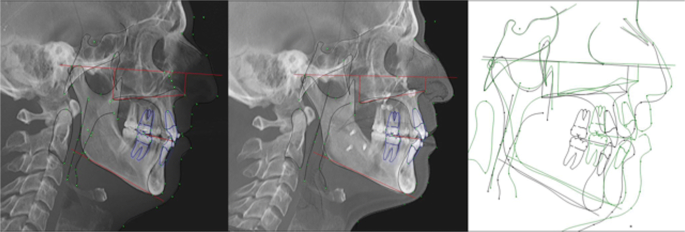

What do you think about this maxillary impaction result?

Personally I think this result is the best I have ever seen

- nose is smaller, midface is shorter,cause nasal base sit higher, gonial angle and ramus remodeled, face is overly shorter and move Has more forward projection in lower and middle third.

When u impact u get soft tissue lost as alfaro hernandez said

I don't see before and after face but he can get better results if he adds posterior downgraft instead of avancing maxilla that much

Philtrum look little odd, if he did posterior downgraft it will have close his nasoabial angle more by 5 to 10 degree and could advance mandibule more

Look at his hyoid to mentum distance, it's good results but not aesthetic based (the case u showed)